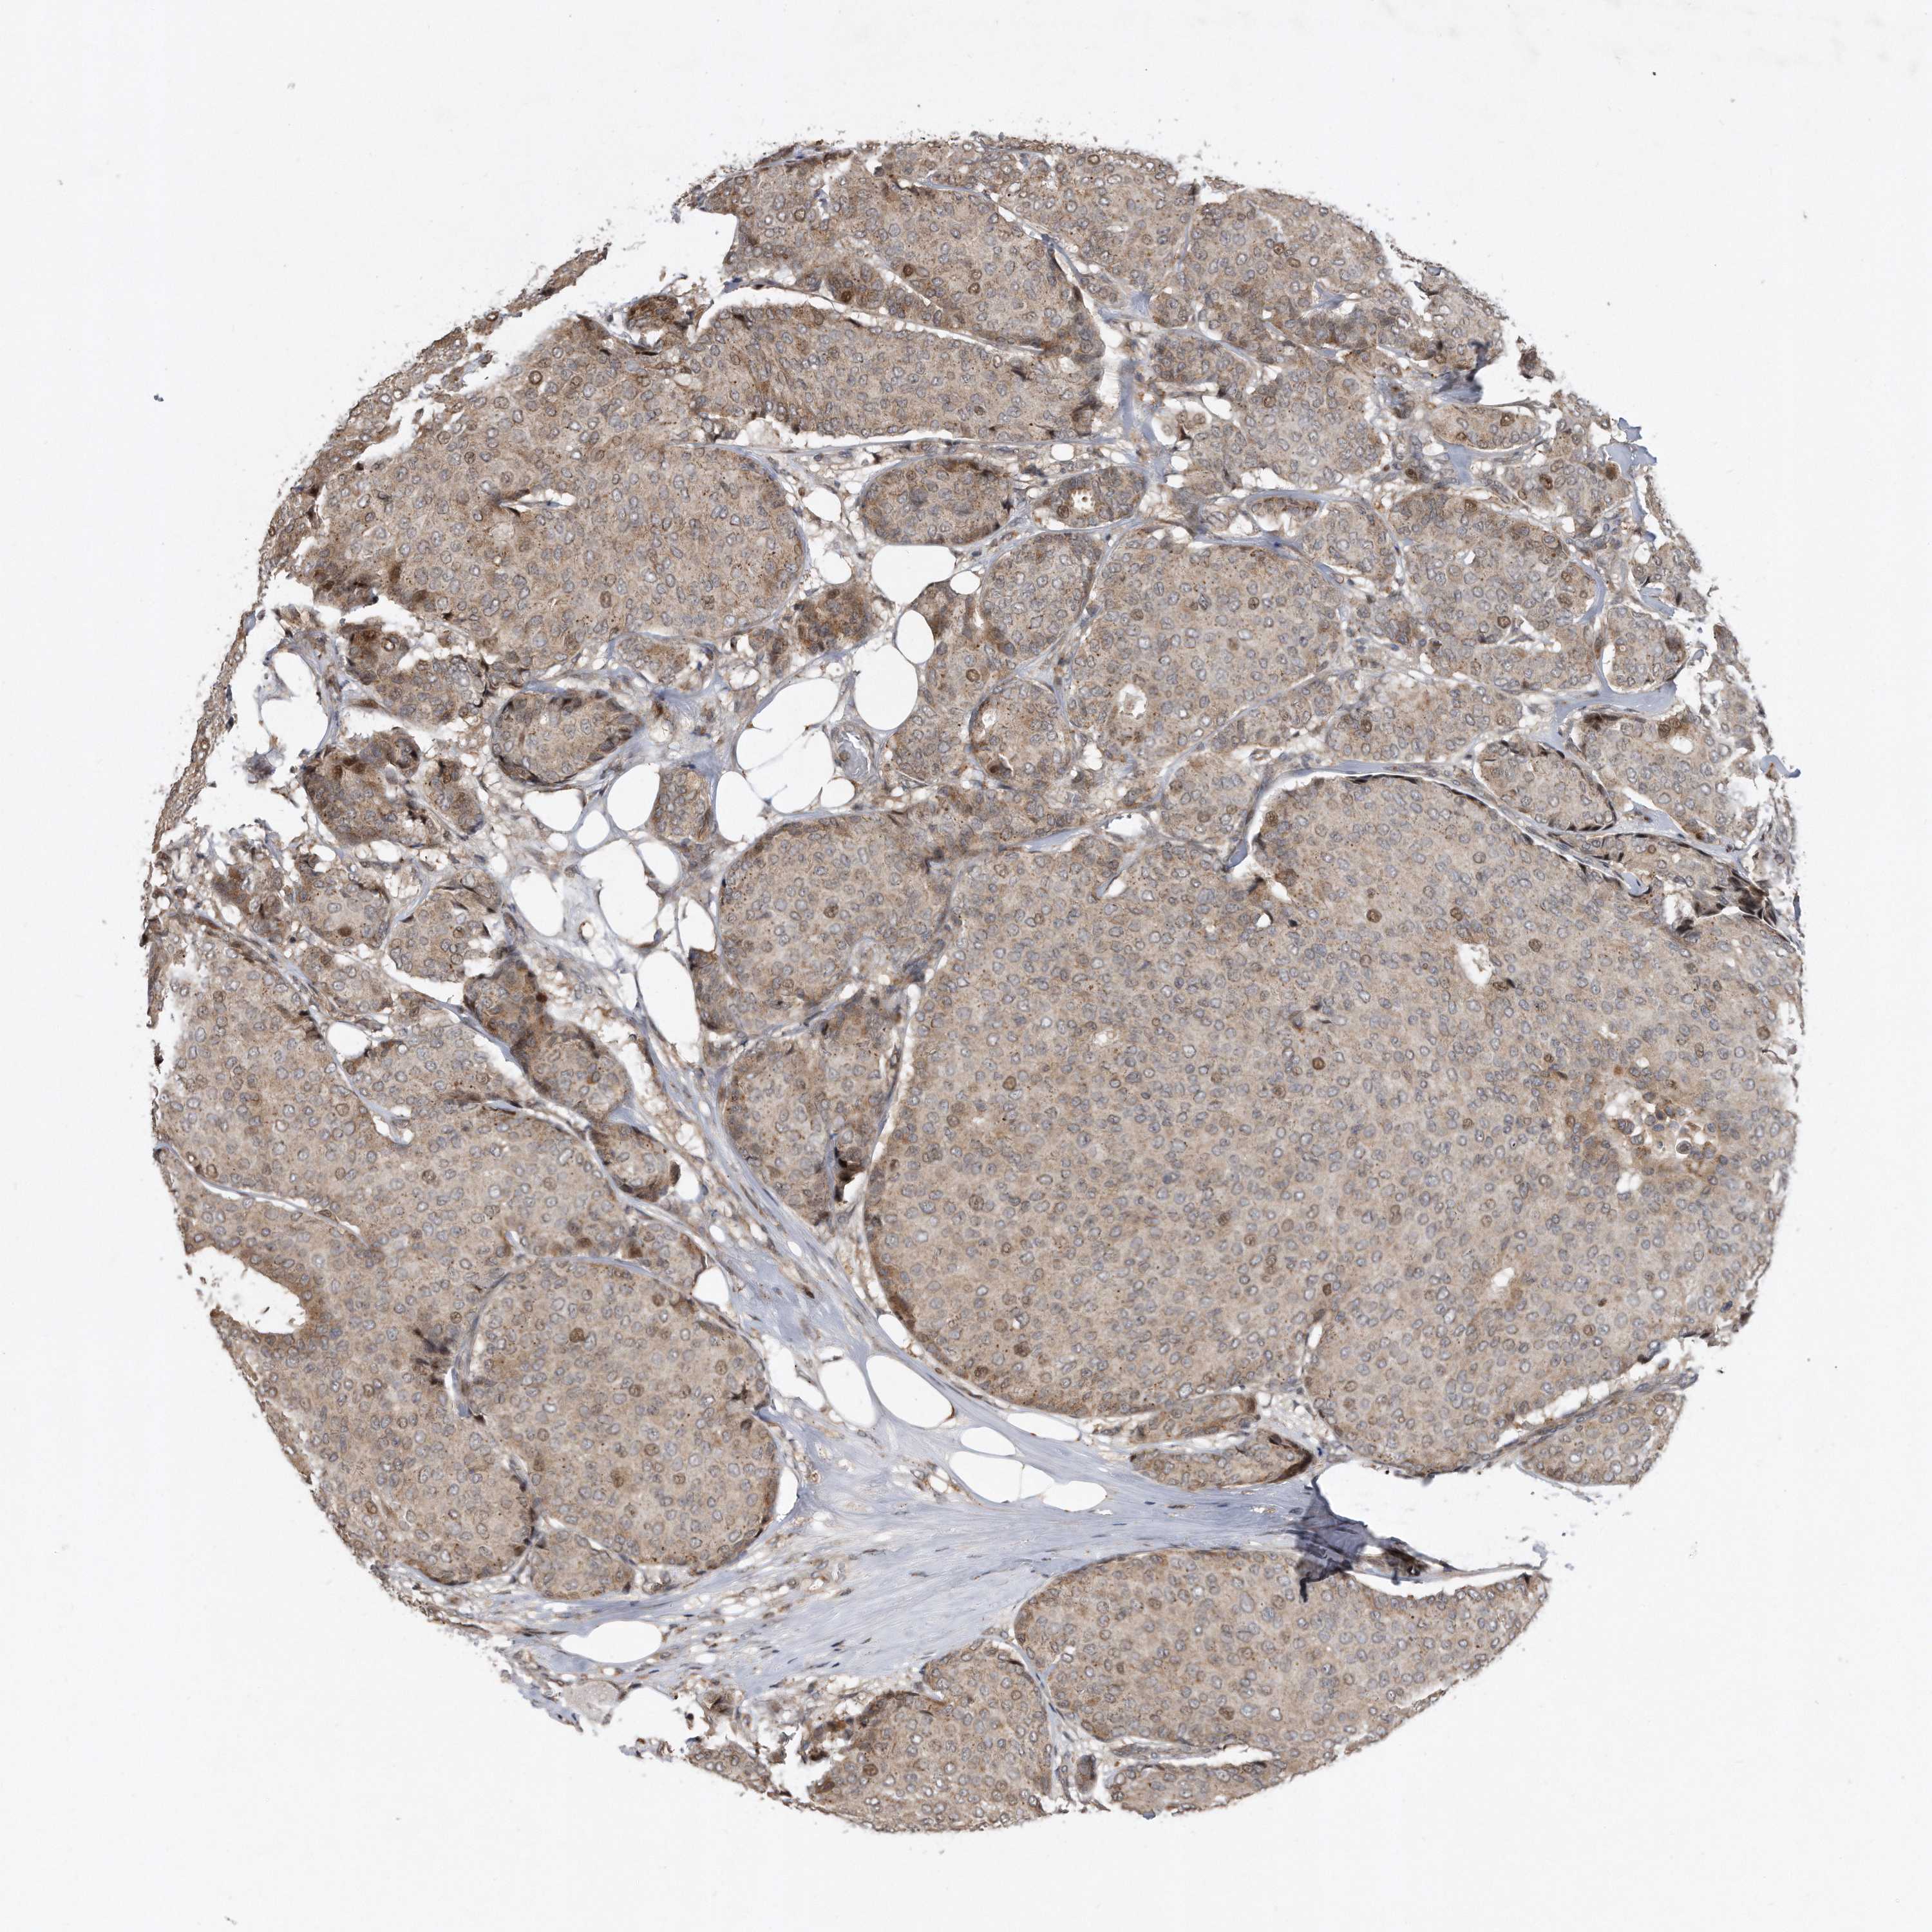

CANCER BREAST CANCER Show tissue menu

BRCA TCGA BRCA VALIDATION PROTEIN EXPRESSION